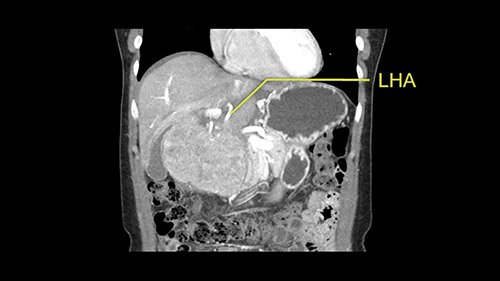

So I have to say that I would do this open, not laparoscopically because of the size of the tumor itself. Upper abdominal incision. Almost certainly, we’d be able to flip this very exophytic lesion up. Intraoperative ultrasound will show the relationship of the tumor and the left portal vein but the dissection at the base of the liver, as I look at things here, I can see the left hepatic artery which sneaks up to the left of the portal vein, should be out of harm’s way so I can take the Segment 2-3 left hepatic artery. The left portal vein is somewhat compressed. But by the time you pull the liver up a bit, you’ll be able to pull that left portal vein out to length and get a good margin on it.

The second is the left hepatic artery. The tumor is displacing the arterial system. So one of the important points which we need to see intraoperatively is to identify and preserve the right artery very carefully and identify the left hepatic artery for ligation.

So in planning for this operation, as I look at the scans, I first visualize the arterial phase and I can see that there’s are a lot of big feeding arteries to this large tumor. Likely all the right side vessels feeding the right side of the liver: right hepatic artery and likely the Segment 4 artery are spared from the tumor. It’s likely the left hepatic artery is ramificating and giving feeding arteries to this tumor. It certainly looks like a large mass that its compressing other structures like the cava, the pancreas, the stomach; but I think there’s a plane and we can see that better in the venous phase. There’s a plane of separation between the gallbladder, the pancreas, the cava, that this tumor is abrupting but likely not invading. Usually, these masses actually don’t invade at that level and basically are pushing the tissues and once you open, you’re able to separate the tumor. Sometimes there’s some adhesions but you can actually separate and there’s usually no invasion.